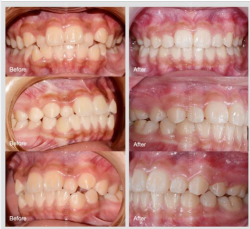

Ca lâm sàng chỉnh nha mắc cài hoàn thành sau hơn 20 tháng

Chẩn đoán chính: | ??̆? ???́? | ??̆?? ??̣? ??̣̂?? | ???? ???́?...làm ảnh hưởng rõ đến thẩm mỹ nụ cười, chức năng ăn nhai và phát âm. Chỉ định điều trị...